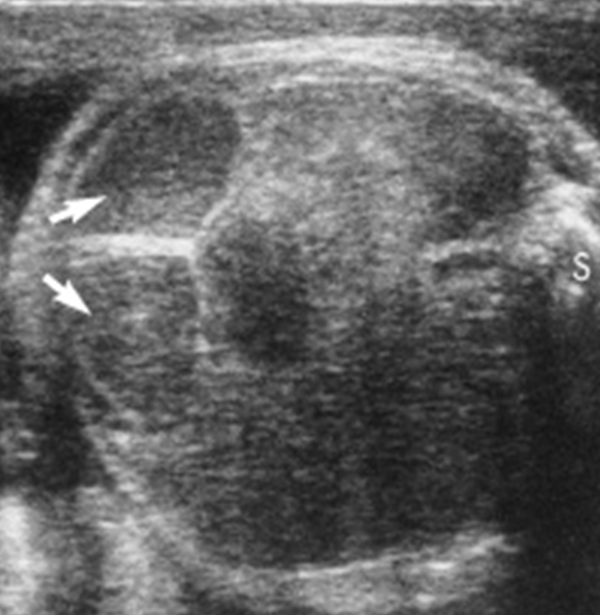

Hydronephrosis - UPJ Obstruction

Hydronephrosis